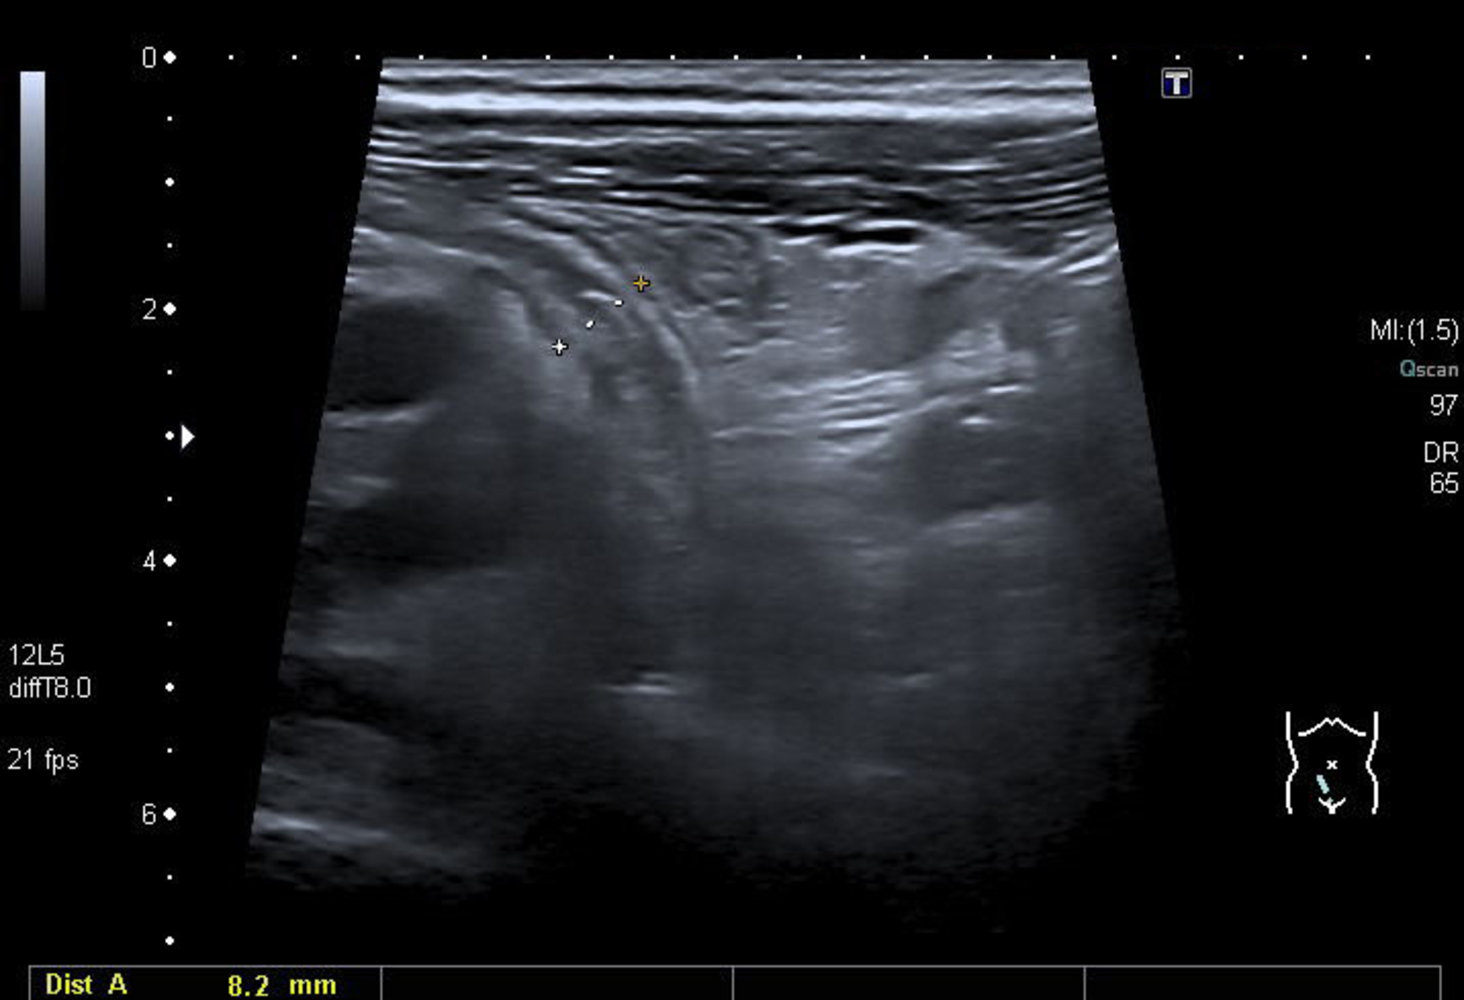

Abdominal ultrasound

Many institutions prefer ultrasound as the initial imaging modality, reserving CT scans for inconclusive ultrasound findings. [11][29]

Supportive findings [32]

- Distended appendix (diameter > 6 mm)

- Noncompressible, aperistaltic, distended appendix

- Target sign: concentric rings of hypo- and hyperechogenicity in the axial/transverse section of the appendix

- Possible appendiceal fecalith: focal hyperechogenicity with posterior acoustic shadowing

While abdominal ultrasound can confirm the diagnosis of acute appendicitis, normal ultrasound findings do not reliably rule out appendicitis. [10]